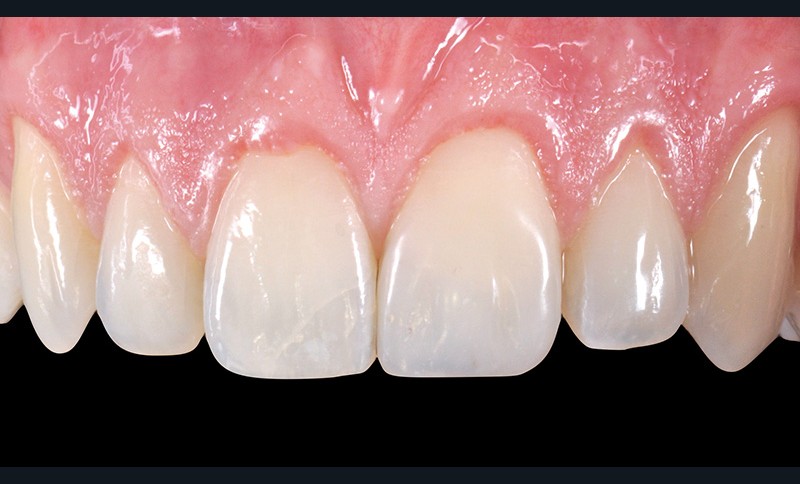

5. Situation à une semaine. La couleur et la forme s’intègrent bien…

6. …mais le travail sur l’état de surface fait clairement défaut. En réalité, la séance de contrôle à une semaine permet d’apporter les éventuelles retouches de teinte ou de forme ou, si besoin, de combler une porosité de surface. Il serait donc contre-productif de travailler la texture de surface dès la première séance.